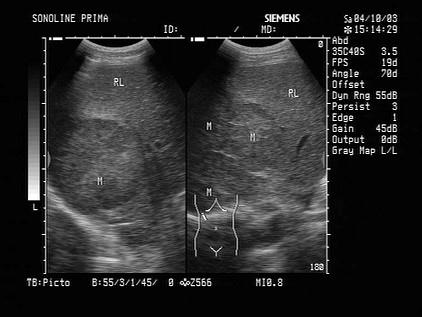

问题 男,35岁,乙肝带菌者,体检时发现肝部异常光团,如图可诊断为?(?)

选项 A.肝癌 B.肝转移癌 C.肝脓肿 D.多发肝血管瘤 E.肝囊肿

答案 A